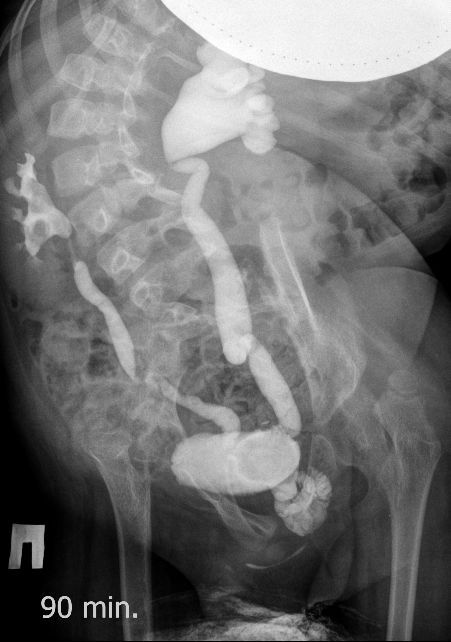

Поскольку откликов нет, добавляю экскреторные урограммы этого же пациента

Нейрогенный мочевой пузырь (?), МКБ, конкремент мочевого пузыря, двухсторонний мегауретер, конкремент правой почки.

Всё верно, только что вот это ?

И что законтрастировалось на экскреторных урограммах около мочевого пузыря?

Стриктура уретры с расширением ее проксимального отдела?

Если честно, и я изначально не совсем понял, где находится конкремент (а это конечно же конкремент), локализованный на урограммах. При первичном исследовании на УЗИ его я не видел (либо он спрятался за тенью конкремента мочевого пузыря, либо я обрадовался редкой находке конкремента такого размера в мочевом пузыре - 2.5 см, и не посмотрел что ниже). Тем не менее при ретроспективном анализе архивированных сонограмм, как мне кажется, он попал в один из сканов, м.б. не совсем чётко.

И всё -же, где конкремент :?:

Возможно, в дивертикуле либо в нижней трети мочеточника..

Верификация:

Выдержка из протокола операции- "...вскрыт мочевой пузырь, обнаружен камень 4 х 3х 2.5 см, плотный, удалён. При дальнейшей ревизии мочевого пузыря обнаружен вколоченный камень в шейке мочевого пузыря и в уретре, удалён камень 2 х 1.5 х 1.5 см. При осмотре устья левого мочеточника - последний зияет, мочеточник расширен до 1 см, учитывая расширение мочеточника, проведена антирефлюксная пластика по Грегуару..."